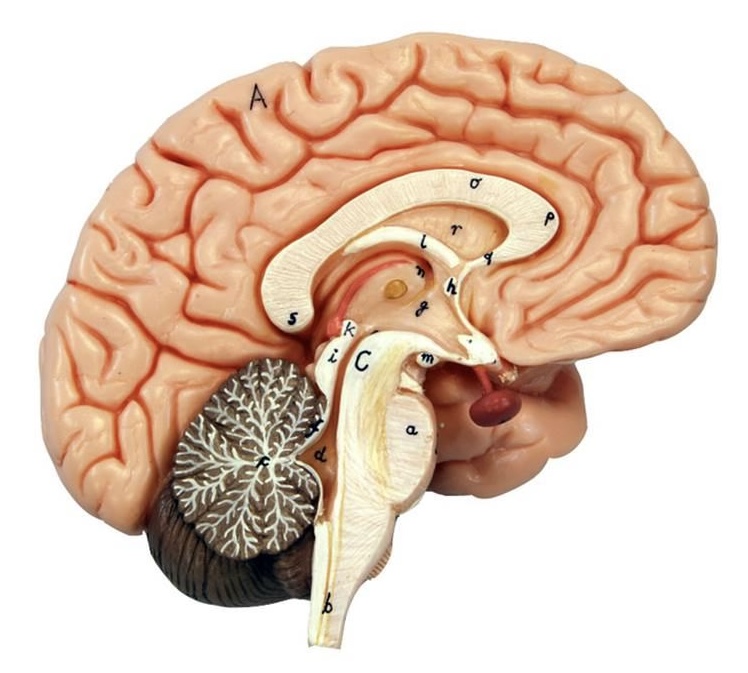

What is D?

lateral ventricle

Imagine thin membrane separating the 2 lateral ventricles

septum pellucidum

What is C?

3rd ventricle

What is B?

cerebral aqueduct

What is A?

4th ventricle

What is below A at the very end?

central canal (spinal cord)

What is C?

midbrain

tectum (corpora quadrigemina): superior colliculus

tectum (corpora quadrigemina): inferior colliculus

What is a?

pons

medulla oblongata

intermediate mass of thalamus

hypothalamus

What is the pink bulb?

pineal gland

corpus callosum

fornix

What is A?

cerebral cortex

cerebral tracts

cerebral hemispheres

longitudinal fissure

What are these ridges?

gyri

What are these shallow grooves?

sulci

Divides parietal from frontal lobe

central sulcus

precentral gyrus

postcentral gyrus